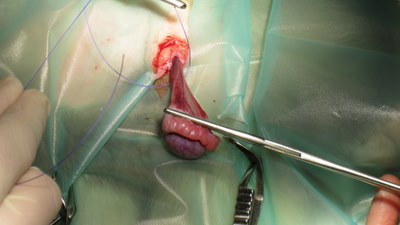

Het testikel komt tevoorschijn

Het testikel en de bijbal worden losgeprepareerd van het scrotum

De testikel wordt afgebonden

De testikel is verwijderd; het lieskanaal staat open